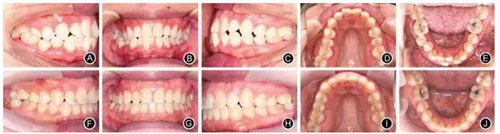

例1:患者女,29歲,主訴要求排齊上下牙列。臨床檢查,雙側(cè)磨牙輕度近中關(guān)系,下牙列中度擁擠,前牙對牙合,右側(cè)后牙反牙合,前牙Bolton比為81.86%。正畸設(shè)計減數(shù)右下中切牙,維持后牙近中關(guān)系。全口固定矯治,上頜牙弓擴大,下頜拔牙間隙用于排齊牙列和適度內(nèi)收下前牙。固定矯治19個月,下頜舌側(cè)固定保持,2年后改為Hawley保持器保持(圖2)。

圖2典型病例1

A.治療前右側(cè)位牙合像 B.治療前正位牙合像

C.治療前左側(cè)位牙合像 D.治療前上頜口內(nèi)像

E.治療前下頜口內(nèi)像 F.治療后右側(cè)位牙合像

G.治療后正位牙合像 H.治療后左側(cè)位牙合像

I.治療后上頜口內(nèi)像 J.治療后下頜口內(nèi)像